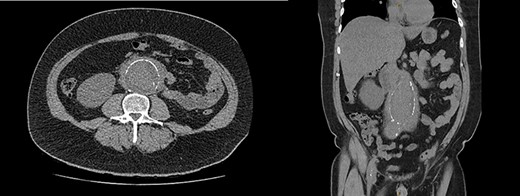

Blood tests demonstrated a severe AKI without significant neutrophilia but a mildly elevated C-reactive protein (Table 1). Given the flank tenderness and AKI, a non-contrast computed tomography of kidney, ureters and bladder (CT-KUB) was performed to exclude a renal or urological pathology. This demonstrated a large infra-renal AAA with surrounding retroperitoneal stranding and bilateral hydronephrosis (Fig. 1).

CT-KUB showing a large fusiform infra-renal AAA with moderate to severe retroperitoneal stranding (white arrow).